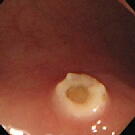

目玉焼きみたい

患者さんは中年の女性 (上段が切除前、下段が切除直後)

ある日の午後、6mmのポリ−プを高周波できれいに焼き切りました。切

除直後発せられた呟きが「目玉焼きみたい」です。 いわれてみると、白み

がきれいに焼けて、黄身が半熟みたいに見えるではありませんか!